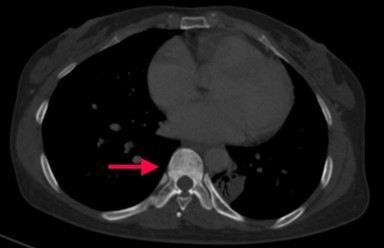

Bệnh nhân đi khám tại bệnh viện Bạch Mai được chụp cắt lớp vi tính lồng ngực phát hiện các đám tổn thương đông đặc phổi 2 bên, tổn thương đặc xương không đều các đốt sống D5, D8, D11 và xương sườn IV bên phải.

Hình 2, 3: Hình ảnh đặc xương không đều các đốt sống D5, D8, D11 và xương sườn IV bên phải.